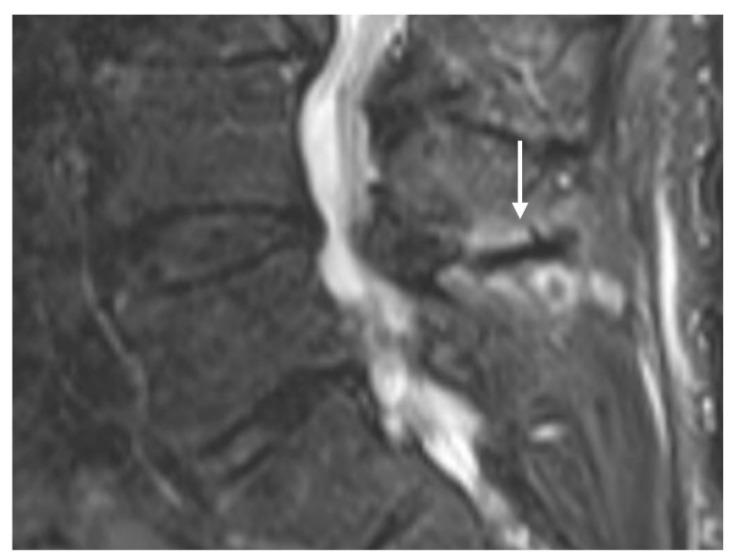

棘突的解剖结构与病理情况

Anatomy and Pathologies of the Spinous Process.

棘突起到肌肉和韧带附着点的杠杆作用。脊柱成像通常作为疼痛和神经根病的诊断检查。在解读这些通常包括X线片、计算机断层扫描(CT)和磁共振成像(MRI)的图像时,可能会遇到无数偶然或意外的发现,既有潜在无症状的,也有有症状的。孤立的棘突病变虽然不太常见,但也是可能遇到的病变类型,可能会带来诊断难题。这些病变范围包括先天性异常、创伤性病变、肿瘤以及炎症性、感染性和代谢性病因引起的病变。专门综述这些病变的文献较为稀少。本文基于作者在一家三级骨科中心10年间通过成像识别出的孤立性棘突病变,综述了一系列影响棘突的病理情况及其相关的影像学特征。为进行本叙述性综述,利用关键词“棘突”在医院图像存档与通信系统(PACS)和放射信息系统(RIS)中进行了检索,并根据影像学报告编制了一份棘突孤立性病变列表。放射科医生在脊柱常规成像中识别出这些病变时,考虑这些病变非常重要。